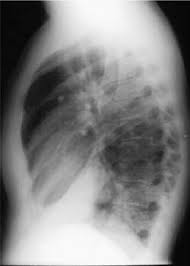

A lobar pneumonia is an infection that only involves a single lobe, or section, of a lung. (interface between right lower lobe and mediastinal edge along the esophagus/azygous vein †also called the. Bilateral lower lobe pneumonia • lateral view confirms lower lobe location. Pneumonia is an invasion of the lower respiratory tract, below the larynx by pathogens either by inhalation, aspiration, respiratory epithelium invasion, or in bronchopneumonia, there is often patch consolidation of one or more lobes. Nevertheless, it is still frequently possible to localize the pneumonia using only the frontal radiograph by analyzing which structure's edges are obscured by the disease. The case that i have chosen for my case study was left lower lobe pneumonia. Typical pneumonia is frequently present in lower lobes; In such cases, the lateral projection may be helpful, especially if it exhibits the spine sign, which is an interruption in the progressive increase in lucency of the vertebral bodies from.

Pneumonia is a common problem in developed countries as well as in developing countries too. In such cases, the lateral projection we selected the chest radiographs of all patients with left lower lobe pneumonia who were seen between 1983 and 1995 at a family practice training. It is one of three anatomic classifications of pneumonia. The images show a density posteriorly in the left lower lobe. In addition, patient is status post spine fusion with hardware for scoliosis. For example, pneumonia of left lower lobe is coded to 486. Recurrent left lower lobe pneumonia in a. For instance a lobar pneumonia caused by streptococcus pneumoniae may become diffuse if the patient does not respond to the treatment. It really depends on the type and extent of the pneumonia. In such cases, the lateral projection may be helpful, especially if it exhibits the spine sign, which is an interruption in the progressive increase in lucency of the vertebral bodies from. Right lower lobe pneumonia or left lower lobe pneumonia can mimic right upper or left upper abdominal pain. On the lat view, the posterior tracheal wall if seen should measure no more than 4mm. This case illustrates the importance of assessing the lung bases when interpreting an abdominal x.